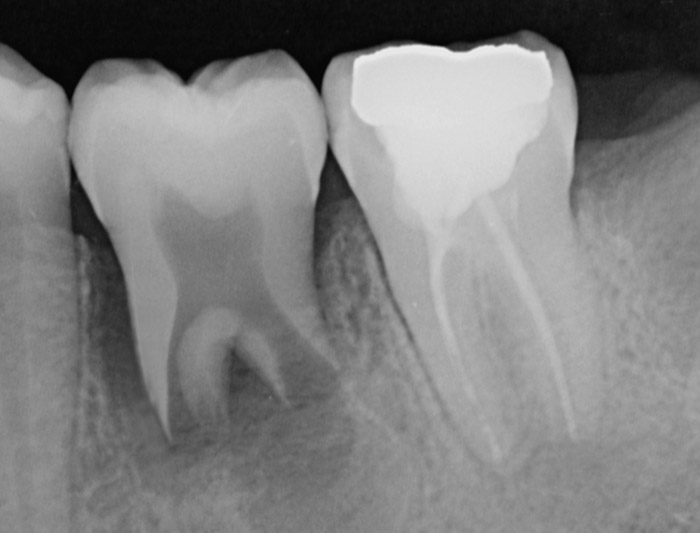

Unter der Transplantation eines Zahnes versteht man die Autotransplantation dh die Einpflanzung eines autologen Zahnes in eine neue Alveole.

Am häufigsten ist die Weisheitszahntransplantation in die Alveole von zumeist nicht erhaltungswürdigen ersten Molaren. Wird der richtige Zeitpunkt des Wurzelwachstums verwendet, kann sich der transplantierte Zahn zu einem wieder vitalen und vollwertigen Zahn entwickeln.